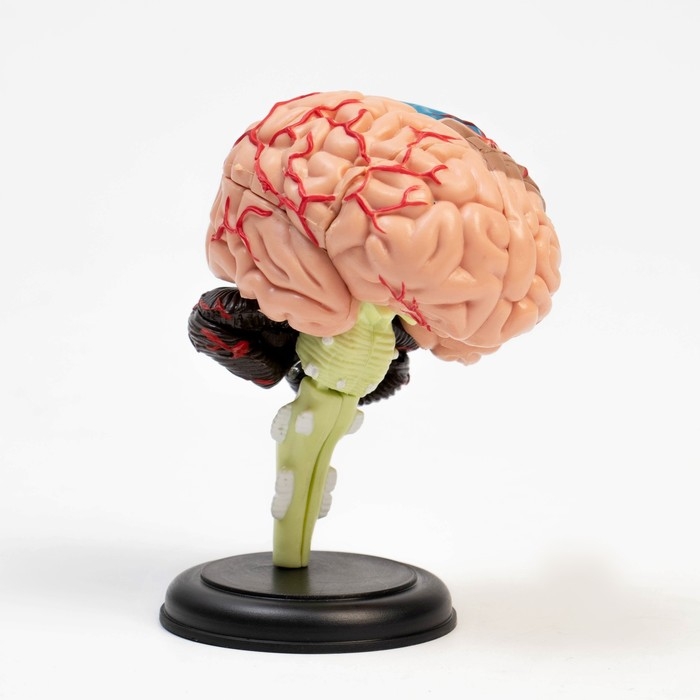

Анатомические модели

ЕКБ 93

No Brand, артикул: 7072363